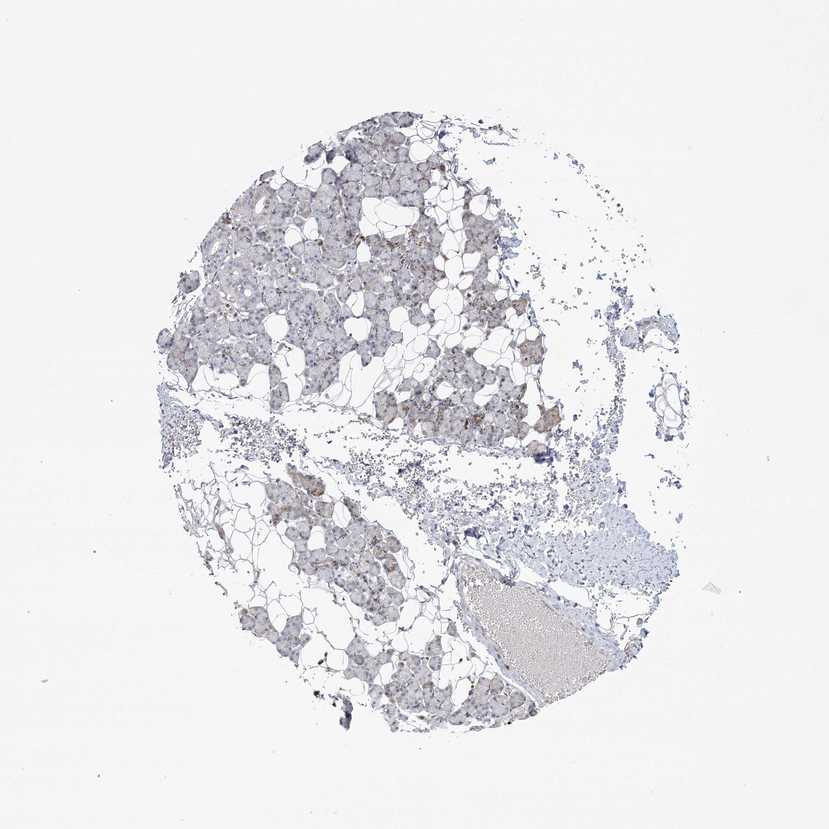

SALIVARY GLAND - Antibody stainingi

Antibody staining in the annotated cell types in the current human tissue is reported as not detected, low, medium, or high, based on conventional immunohistochemistry profiling in selected tissues. This score is based on the combination of the staining intensity and fraction of stained cells.

Each image is clickable and will lead to virtual microscopy that enables deeper exploration of all samples and also displays staining intensity scores, fraction scores and subcellular localization as well as patient and tissue information for each sample.

Antibody HPA036144Antibody HPA036145

Glandular cells Not detectedMedium